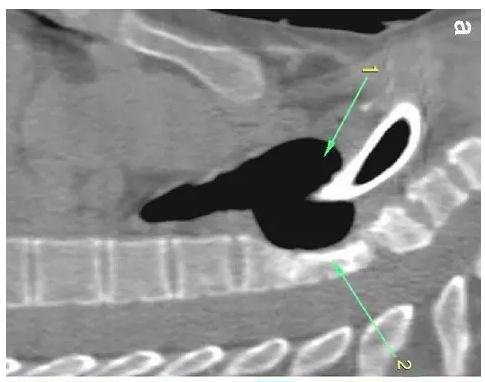

胸部CT顯示氣切套管氣囊周圍氣管擴張,胸1-4椎體前部受到侵蝕(下圖a-c)���。

下圖箭頭1為氣切套管氣囊緊貼T1-4椎體水平��,造成椎體前部受到侵蝕(箭頭2):